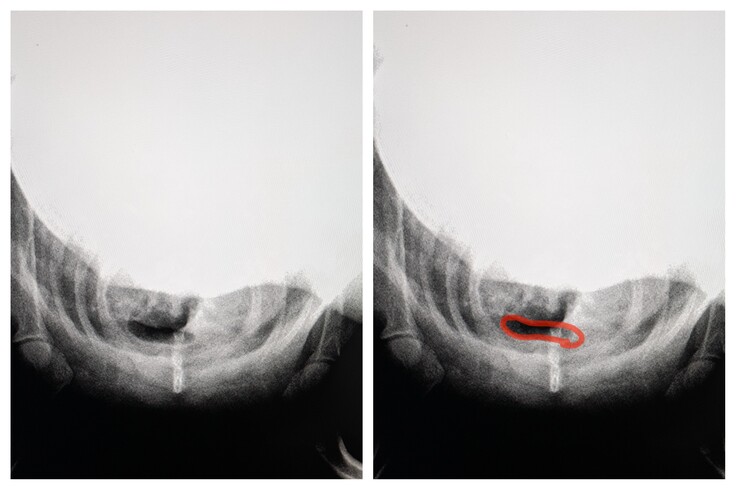

▲喉の方からみたポンタの気管。本来、まん丸のはずが楕円につぶれてしまっています。